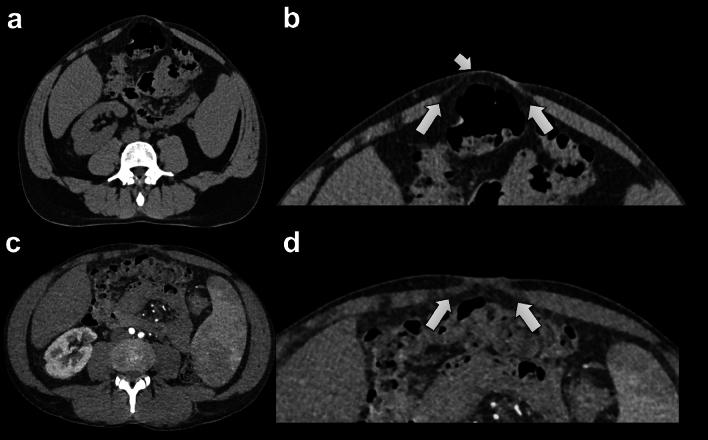

To investigate the differences in the visibility and size of abdominal wall hernias in computed tomography (CT) with and without Valsalva maneuver.

This single-center retrospective study included consecutive patients who underwent abdominal CTs with Valsalva maneuver between January 2018 and January 2022. Inclusion criteria was availability of an additional non-Valsalva CT within 6 months. A combined reference standard including clinical and surgical findings was used. Two independent, blinded radiologists measured the hernia sac size and rated hernia visibility on CTs with and without Valsalva. Differences were tested with a Wilcoxon signed rank test and McNemar's test.

The final population included 95 patients (16 women; mean age 46 ± 11.6 years) with 205 hernias. Median hernia sac size on Valsalva CT was 31 mm compared with 24 mm on non-Valsalva CT (p < 0.001). In 73 and 82% of cases, the hernias were better visible on CT with Valsalva as compared to that without. 14 and 17% of hernias were only visible on the Valsalva CT. Hernia visibility on non-Valsalva CT varied according to subtype, with only 0 and 3% of umbilical hernias not being visible compared with 43% of femoral hernias.

Abdominal wall hernias are larger and better visible on Valsalva CT compared with non-Valsalva CT in a significant proportion of patients and some hernias are only visible on the Valsalva CT. Therefore, this method should be preferred for the evaluation of abdominal wall hernias.